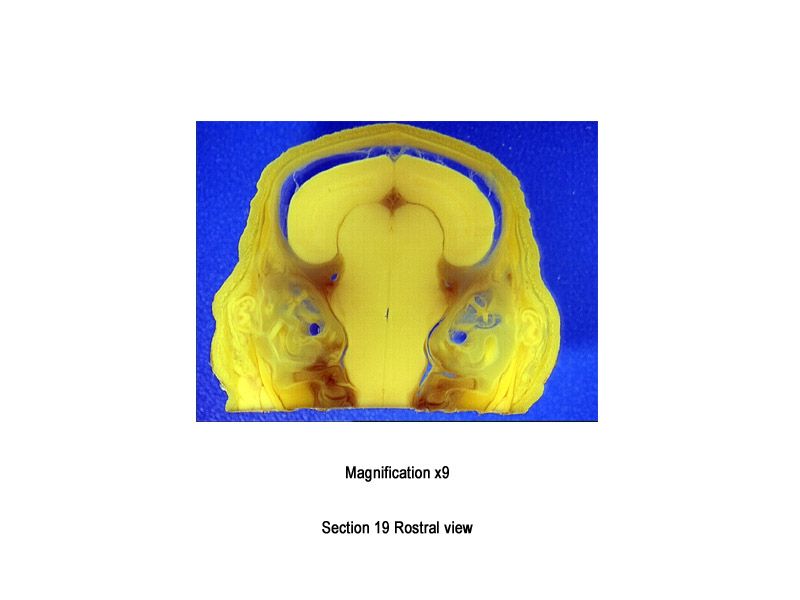

The images below show the normal appearance of Bouin's fluid fixed head sections in specimens at Day 29 of gestation (day mating observed = Day 0).

It is essential that both sides of each section is examined so that structures that exist is several sections can be visualised by the examiner in their mind as 3D.